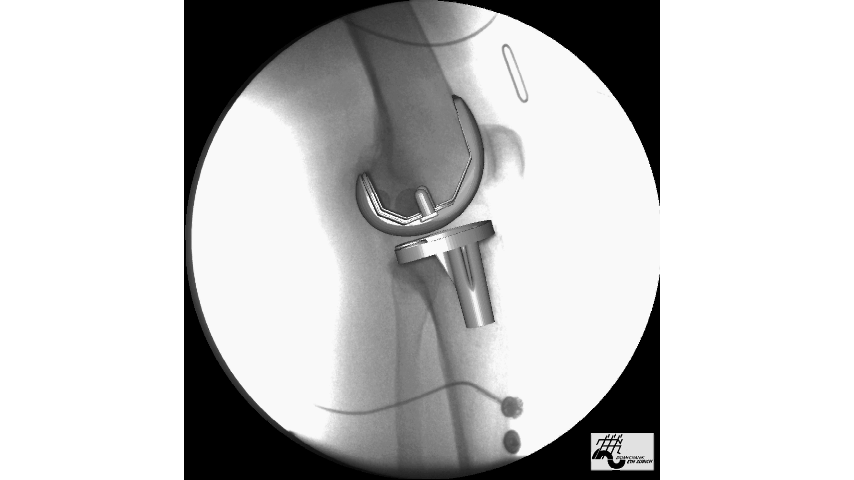

- traitement chirurgicalDans le passé, pour les patients souffrant d'une arthrose avancée plus sévère, nous procédions généralement à une intervention chirurgicale.Remplacement total de la surface du genou (hanche)En d'autres termes, la surface cartilagineuse usée est remplacée par une surface métallique, ce qui est similaire au processus de remplacement d'une prothèse dentaire par un appareil dentaire, et la surface cartilagineuse usée est remplacée par une surface métallique. Cette procédure est relativement plus invasive et certains patients ont tendance à avoir une usure plus importante du cartilage d'un côté de l'articulation, par exemple, le côté médial ou latéral est très usé, il est donc très pénible de devoir remplacer la partie la moins usée par une prothèse totale du genou. Par conséquent, de nos jours, nous préconisons également des traitements épargnant le genou, qui peuvent être effectués par ostéotomie et traitement orthopédique, ou par un remplacement d'un seul compartiment, afin d'essayer d'aider les patients les plus sévères à résoudre leurs problèmes. Le problème peut être résolu par l'ostéotomie et le traitement orthopédique, ou par le remplacement d'un seul compartiment. Bien entendu, le remplacement total de l'articulation est nécessaire pour les patients souffrant d'une arthrose avancée et particulièrement grave.

C'est avant tout pour lesUne petite introduction à la thérapie par étapes pour les patients souffrant d'arthroseNous devons souvent prendre d'abord des mesures simples et moins coûteuses, puis choisir des mesures relativement plus traumatisantes pour aider les patients à contrôler leurs symptômes, et s'ils ne trouvent toujours pas de soulagement, il se peut qu'ils doivent finalement subir une opération chirurgicale pour les aider à résoudre leurs problèmes.

Il est important que les patients souffrant d'arthrose comprennent que la maladie peut être complètement guérie si les symptômes du patient atteignent un stade avancé, ce qui signifie que l'arthroplastie peut aider le patient à résoudre complètement le problème.

Mais après tout, cette mesure comporte un certain risque, et le coût et le traumatisme de l'opération sont relativement élevés, de sorte que de nombreux patients ne choisissent pas cette mesure thérapeutique.

Et pour les personnes souffrant d'arthrose qui veulent vraiment essayer de l'éviter, en subissant une intervention chirurgicale pour résoudre le problème.Il est important de parler à votre médecin dès que vos articulations présentent des symptômes et de chercher de l'aide auprès de votre médecin le plus tôt possible.Plus le traitement est précoce, meilleurs seront les résultats et plus il sera simple, moins coûteux et moins traumatisant de contenir le problème et de ne pas laisser la maladie progresser à un stade avancé.